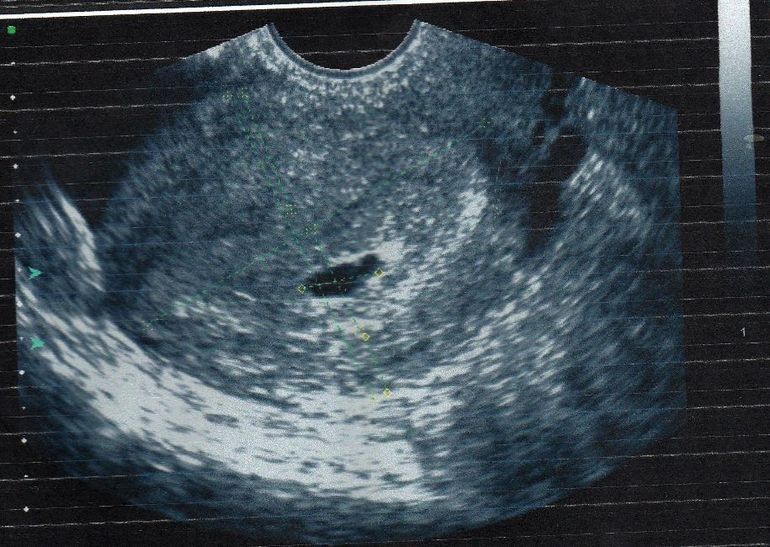

узи 5-6 недель)

Срок по месячным 6 нед.5 дней,а по узи 5нед.5 д,но это вроде как нестрашно...

Сердечко бьется...так странно было слышать сердцебиение совсем крошечного,еще не знакомого человечка)))....140 ударов в минуту,КТР 3,8 мм))

Даже не верится что темненькое пятнышко на фото - моя малявочка)))такая кроха))